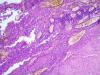

Опухоль матки |

Гистокартина больше соответствует на эндометриальную стромальную опухоль. Кроме очага кровоизлияния с очагом некроза, наблюдается стромальные округлые клетки без патологических митозов.

нме тоже похожа на эпителиоидную лейомиому.

В представленном рисунке наблюдается со светлой и эозинофильной цитоплазмой клетки округлым мономорфными ядрами, участки некроза с геморрагией и некрозом напоминает на эндометриальные стромальные узелки. А светлая цитоплазма, местами с эозинофилией клеток указывает о наличии гликогена, которые встречаются и при дисгерминоме у женщин от 20 до 40 лет. Пока идет гадание в кофейной гуще